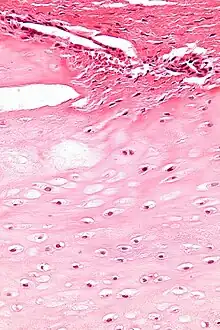

Micrograph of an enchondroma. H&E stain. |